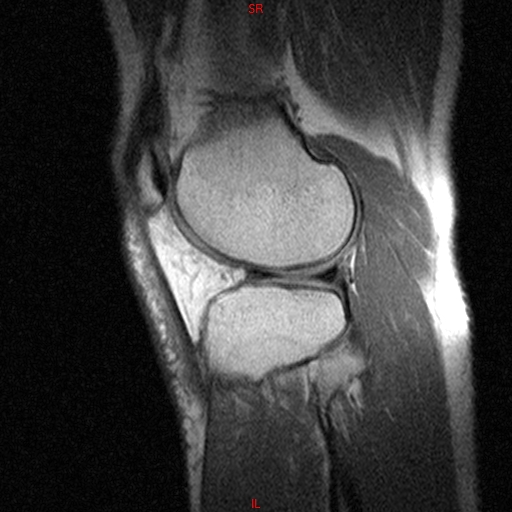

• RESONANCIA NORMAL RODILLA SAG DENSIDAD PROTONICA

• RESONANCIA NORMAL RODILLA SAG T1